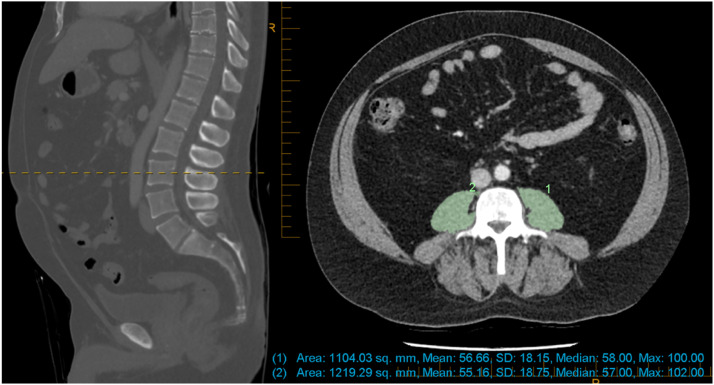

Background: CT measurements of psoas muscle density (PMD) and area (PMA) (with or without indexing to height-squared or body-surface-area) are used interchangeably as sarcopenia measures - it is unknown which best correlates with surgical risk.

Objectives: 1.Determine the correlation between psoas muscle density, area, and indexed area; 2.Identify which psoas measures most strongly associated with surgical outcomes DESIGN: The University Hospital Geelong Colorectal database included all patients who underwent elective colorectal surgery from 2007 to 2014 (minimum five-years follow-up). Pre-operative CT scans were reviewed, psoas measures correlated with each other and with outcomes.

Exposure: Psoas muscle density, area, and area indexed by height-squared and body-surface-area.